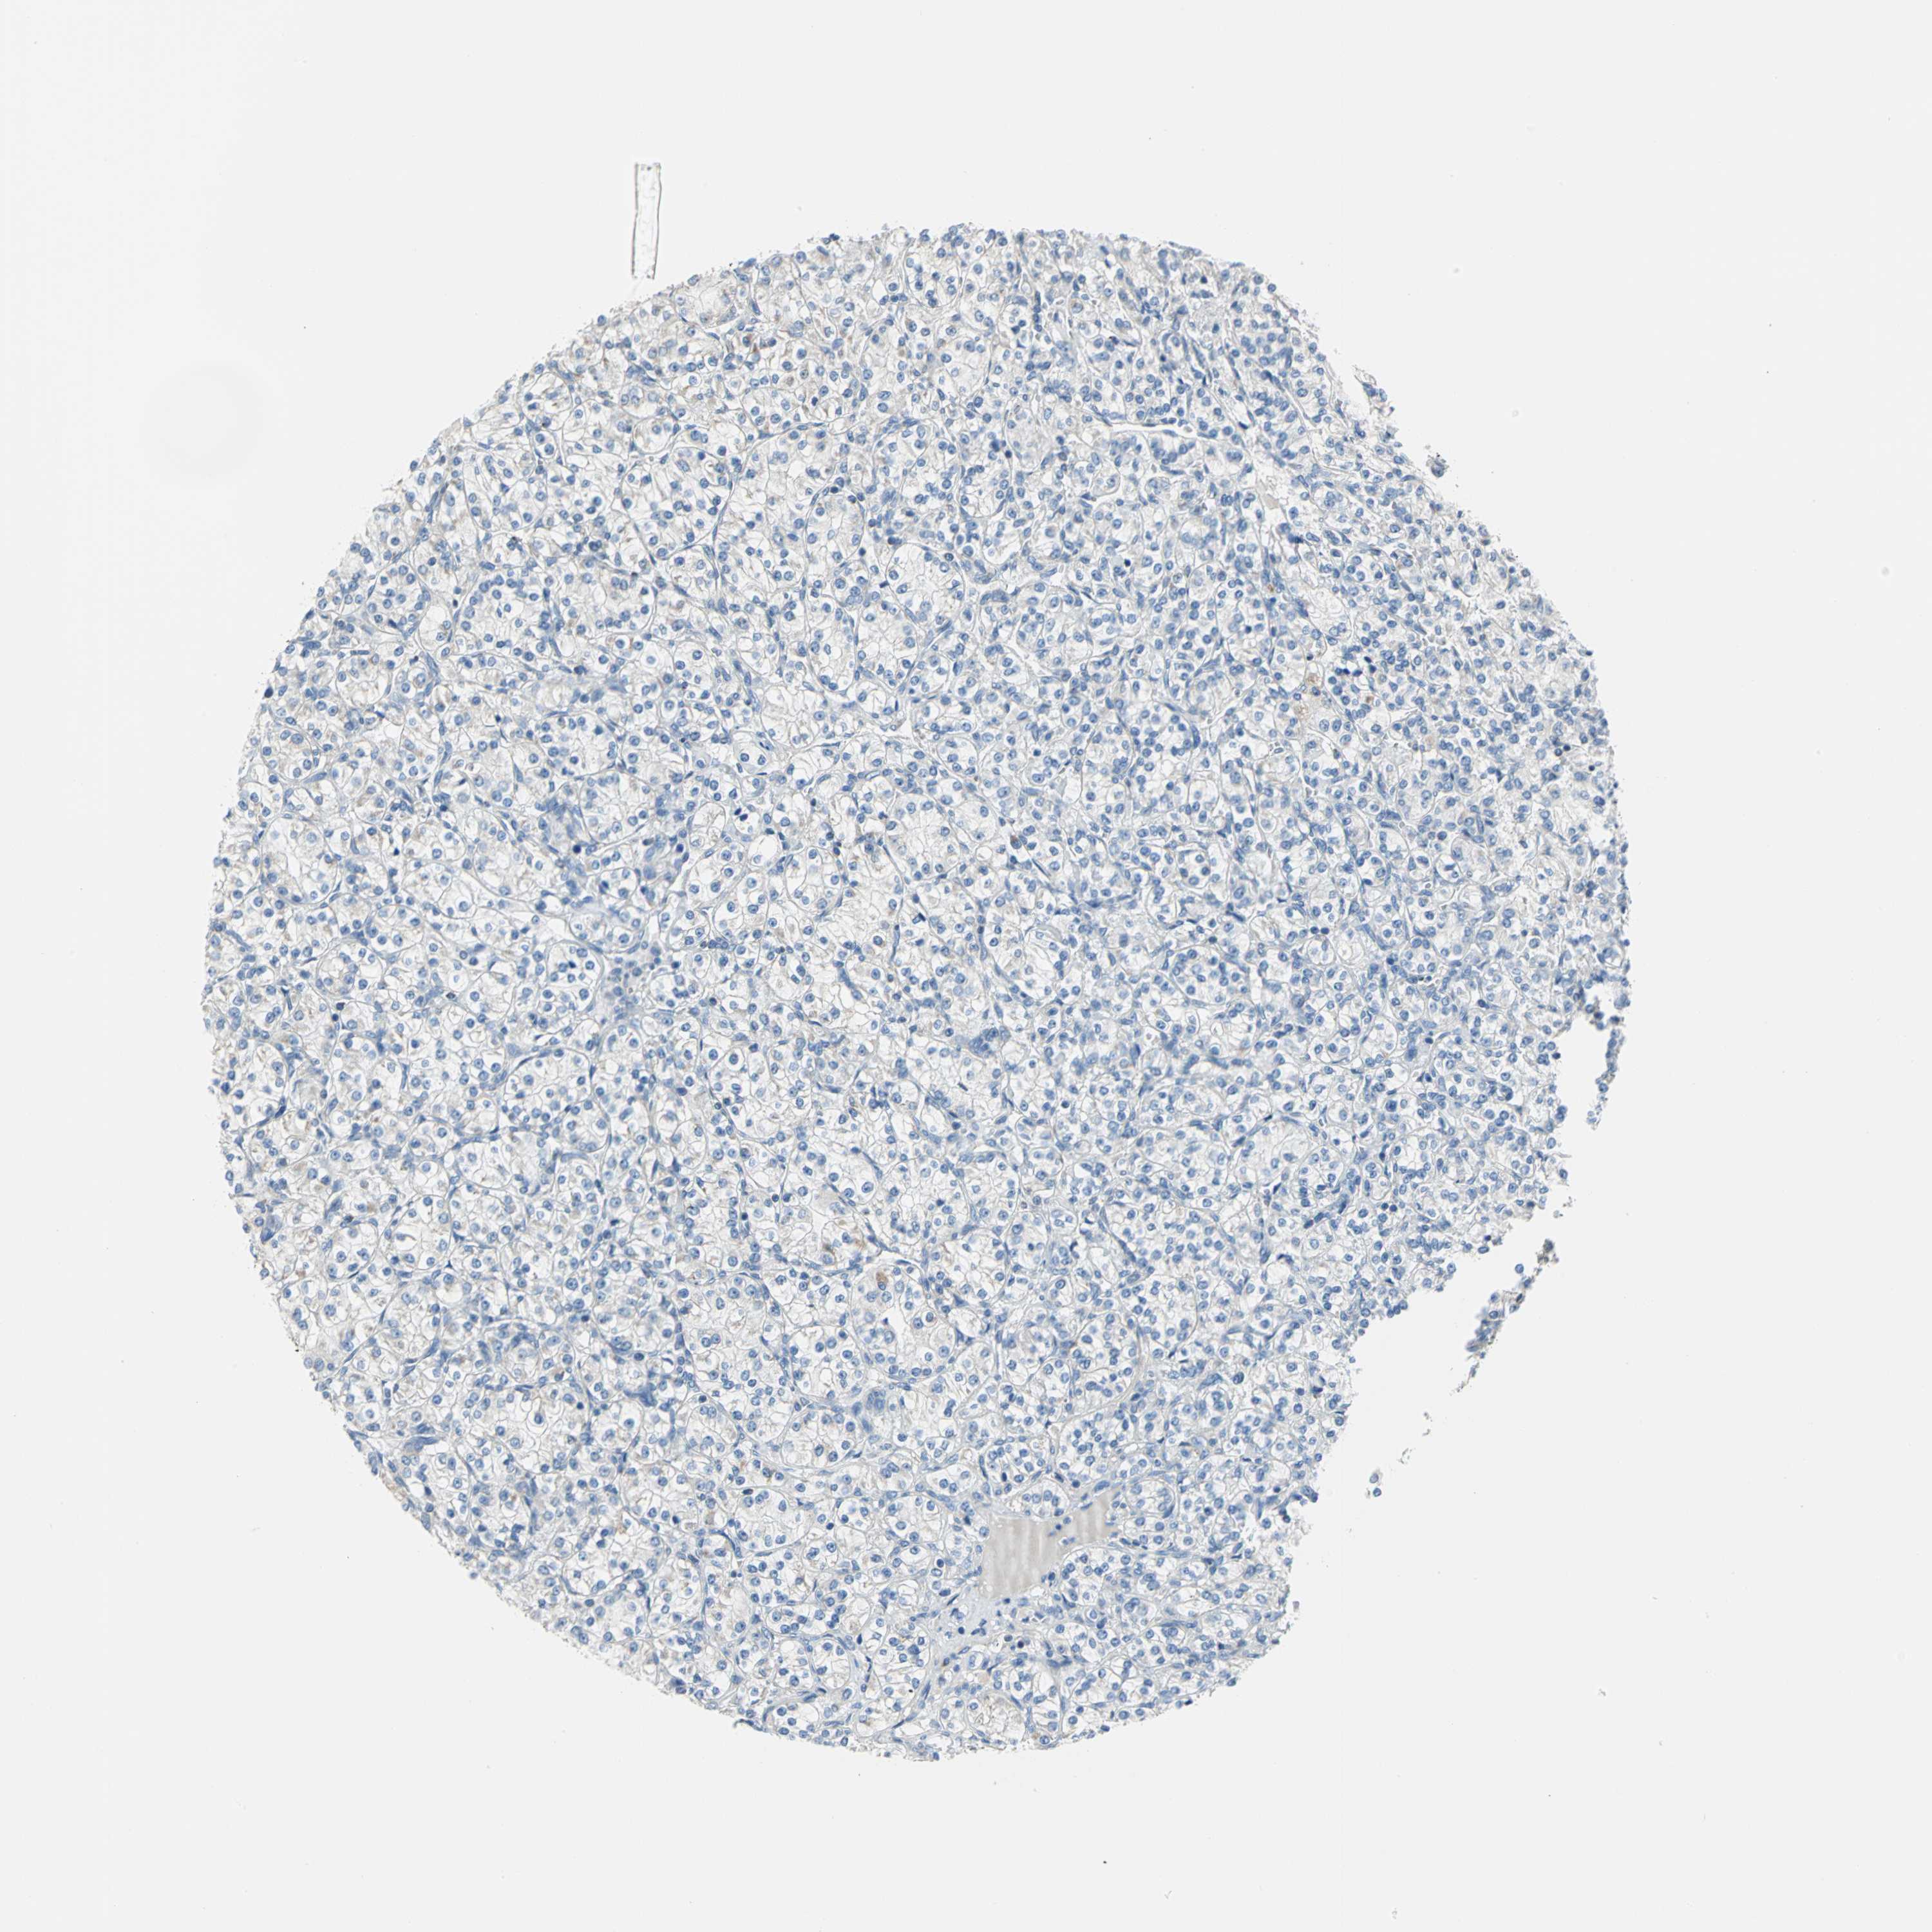

CANCER RENAL CANCER Show tissue menu

KICH TCGA KIRC TCGA KIRC VALIDATION KIRP TCGA PROTEIN RCC CPTAC PROTEIN EXPRESSION